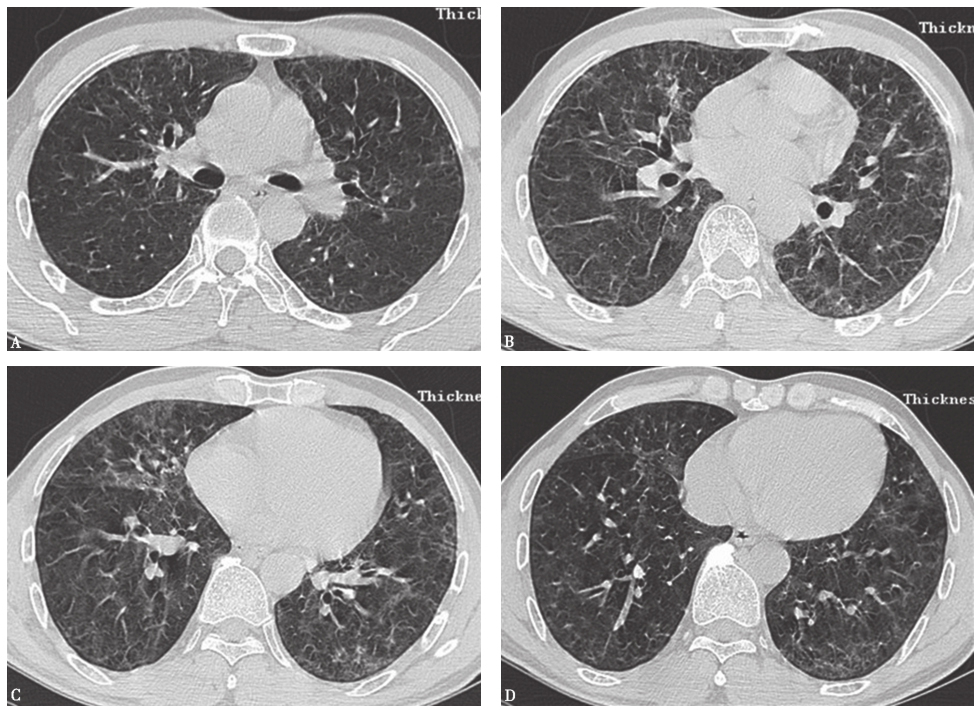

患者经泼尼松(20mg,每天2次)口服治疗,并且脱离原有工作环境,1个月后复查胸部HRCT示两肺磨玻璃影及小结节影较前进一步吸收(图17),咳嗽、气喘症状明显缓解。

图17泼尼松治疗1个月后胸部HRCT表现-6902304544819200

图17泼尼松治疗1个月后胸部HRCT表现

HRCT显示磨玻璃影及小结节影进一步减少,双肺胸膜下少量小结节影